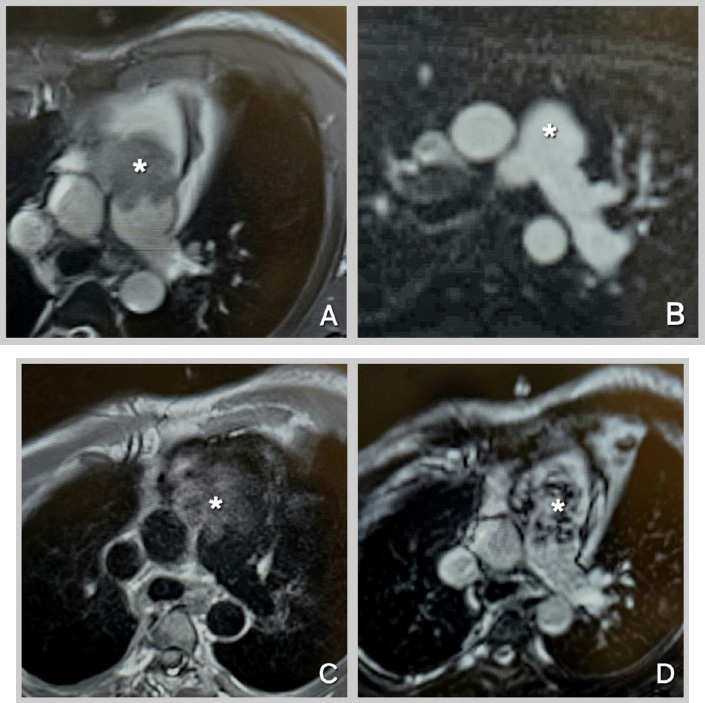

The patient was further investigated with computed tomography (CT), cardiac magnetic resonance imaging (MRI), and positron emission tomography-computed tomography (PET-CT). The CT scan showed a mass extending from the RVOT into the main pulmonary trunk, causing significant stenosis. PET/CT showed a fluorodeoxyglucose (FDG) avid lesion in the right ventricular outflow tract region extending to the right main pulmonary artery and the lobar arteries (Fig. 2A-D). Cardiac MRI showed an enhancing filling defect within the RVOT, main, and right pulmonary arteries, suggestive of a neoplastic process, most probably a pulmonary artery angiosarcoma. Signs of right heart volume and pressure overload were also seen (Fig. 3A-D). The patient also had a right-sided pleural effusion.

Cardiac MRI Sequences for Mass Characterization.

(A): Cine-SSFP (Cine-steady state free precession) sequence at the level of the great vessels, showing an iso-heterogeneous mass in the main pulmonary artery extending from the right ventricular outflow tract (RVOT). (B): Perfusion sequence at the level of the great vessels, demonstrating hyperenhancement of the mass. (C): T1-weighted sequence at the level of the great vessels, revealing an iso-hyper heterogeneous mass in the main pulmonary artery extending from the RVOT. (D): Late Gadolinium Enhancement sequence at the level of the great vessels, showing an iso-hyper heterogeneous mass in the main pulmonary artery extending from the RVOT. Mass indicated by Asterix.